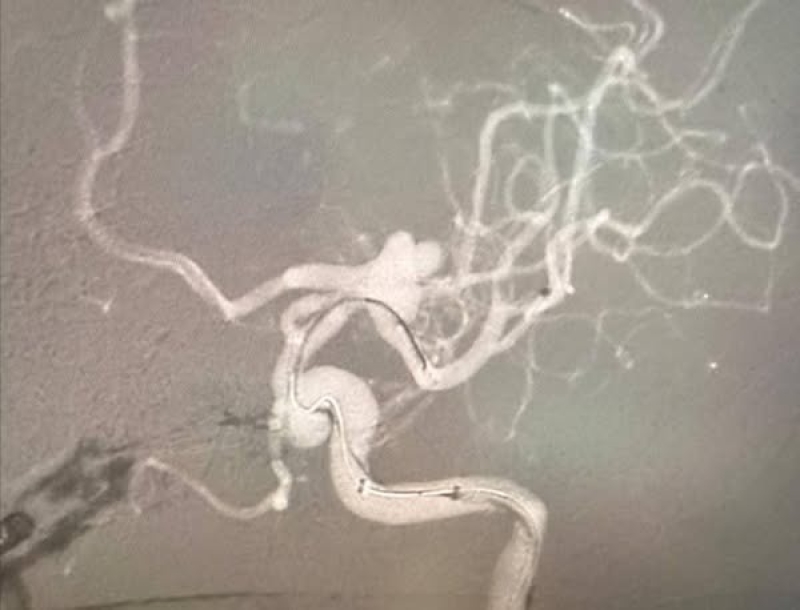

خبرني - تمكّن فريق طبي متخصص في مستشفى الملك المؤسس عبدالله الجامعي من إنقاذ حياة مريض يبلغ من العمر 57 عامًا، كان يعاني من نزيف دماغي حاد ناتج عن انفجار أمّ الدم في الشريان السباتي الداخلي وتفرع الشريان الدماغي الأمامي مع الأوسط .

وخلال العملية، تم تركيب شبكة دقيقة بين الشريان الدماغي الأوسط والشريان السباتي الداخلي، ما ساعد على تحويل مسار الدم بعيدًا عن الكيس الدموي المنفجر، وبالتالي وقف النزيف بشكل كامل .

وأوضح الأستاذ الدكتور موفق الحيص أن هذه العملية تُعد من العمليات المعقدة والدقيقة جدًا، وتتطلب مهارة عالية في التعامل مع الأوعية الدموية الدماغية، مشيرًا إلى أن المستشفى يمتلك كوادر طبية مؤهلة وأجهزة متطورة تمكّنه من إجراء مثل هذه التدخلات العصبية الدقيقة .